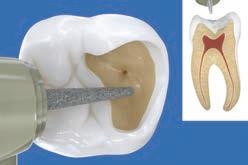

PROCEDURE

dentin) with slow-speed round bur or excavator. To control overexcavating near the pulp, remove final portion of caries with hand excavator.